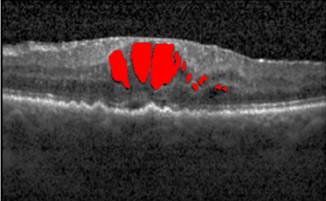

Recent works suggest novel deep learning tools for detection, segmentation and characterization of eye disorders. Accurate segmentation of retinal fundus lesions and anomalies in imaging